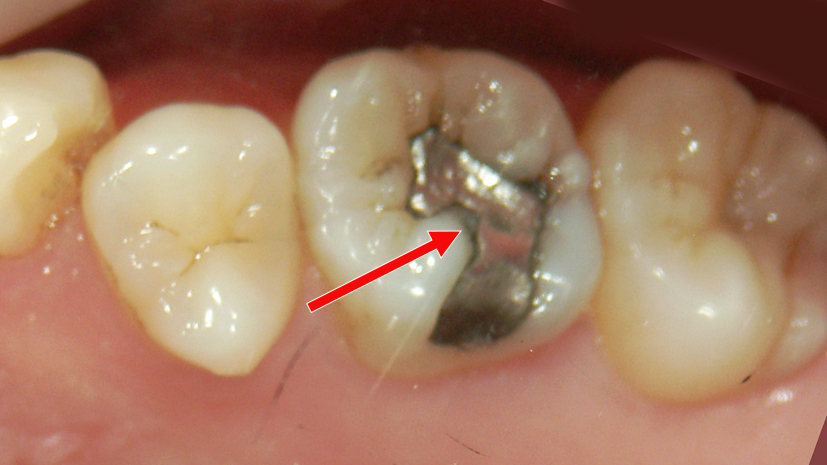

二次カリエスを起こしたアマルガム充填症例

画像は右下第1大臼歯(6番)の頬側面を示しています。矢印で示された部位にアマルガム充填が施されています。アマルガムは銀色の金属充填材で、かつて虫歯治療によく使われていました。

充填部の周囲に黒ずみ(変色)や境界のわずかな段差が見られ、充填の劣化や**二次カリエス(二次う蝕)**の可能性が高い状態です。これは、充填材と歯質の間にわずかな隙間が生じ、そこに細菌が侵入して再び虫歯が発生するケースです。

解説まとめ

- 部位:右下第1大臼歯(6番)頬側

- 処置歴:アマルガム充填(旧来の金属修復)

- 現状:充填境界部に変色と隙間 → 二次カリエス疑い

- リスク:虫歯の進行による象牙質・神経への感染リスク

- 推奨治療:古いアマルガムの除去後、う蝕除去を行い、コンポジットレジン(白い樹脂)による再修復が望ましいです。

審美面・健康面の両方から、早めの再治療が推奨される症例です。